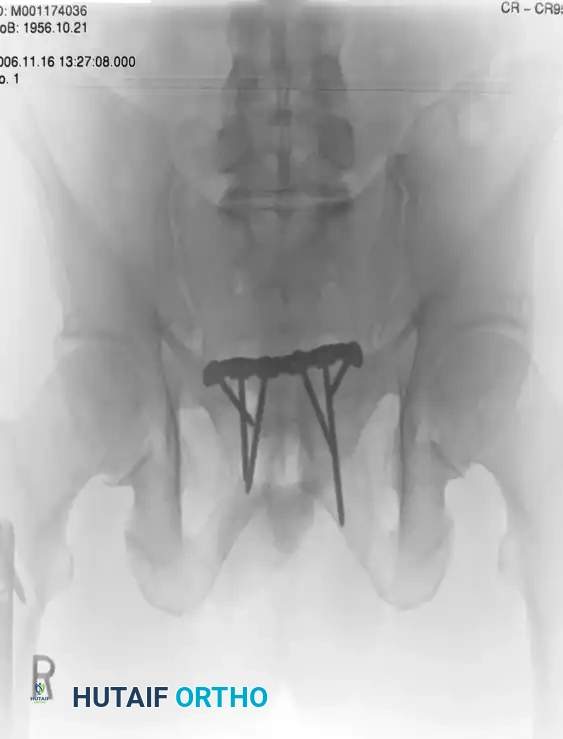

Case 1: Young-Burgess Anteroposterior Compression Type II (AP II)

An AP II injury is characterized by an "open book" pelvis. The mechanism is a direct anterior-to-posterior force causing symphyseal diastasis (>2.5 cm) and disruption of the anterior sacroiliac, sacrotuberous, and sacrospinous ligaments. The posterior sacroiliac ligaments remain intact, preventing vertical translation but allowing rotational instability.

The preoperative AP view demonstrates significant widening of the symphysis pubis.

Treatment typically involves anterior fixation. The patient is positioned supine. A Pfannenstiel approach is utilized to access the symphysis. A multi-hole symphyseal plate is applied with alternating fully threaded cortical screws to reduce and stabilize the diastasis.

Postoperative Imaging:

Postoperative AP, inlet, and outlet views confirm anatomic reduction of the anterior ring and restoration of pelvic volume.

FIGURE 56-43: Young and Burgess anteroposterior type II (AP II) pelvic ring injury with pubic diastasis treated with anterior fixation. A and B, Preoperative views. C-E, Postoperative anteroposterior, inlet, and outlet views.